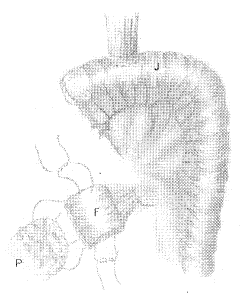

图2 利用代胃空肠(J)制作带血蒂浆肌瓣(F)贴敷保护胰腺残端(P)

施行胃扩大根治切除时,先在肝十二指肠韧带外侧剥离,向下翻起十二指肠以清除肝十二指肠韧带和胰十二指肠后的淋巴结。在暴露腹腔动脉及其分支后,分别在脾动脉和胃左动脉根部切断。然后将胰腺翻起,于其深面切断结扎脾静脉,随后切除远端胰腺。切断胰腺时,近端稍外凸,呈>形,然后结扎主胰管,断面缝扎止血(图1A)。最后游离脾脏、胃底部和食管下端,切断双侧胃迷走神经,即可将胃全部连同脾脏、胰体尾部及其浅、深组淋巴结一并整块切除。完成切除后,从拟行代胃的空肠断端制作带血管蒂浆肌瓣。先从距空肠断端约20 cm处行食管空肠端侧吻合,再将断端空肠5 cm切断,纵行切开其对系膜缘,粘膜下注射生理盐水,锐性剥离粘膜,保留粘膜下层,创面止血后修剪成大小与胰腺断面相当的浆肌瓣。这样,从食管空肠吻合口到浆肌瓣之间牺牲一段大约10 cm的空肠。分离其系膜需紧贴肠壁,以保护瓣片的血供。然后,在接近吻合口5 cm处关闭空肠断端。最后用纤维蛋白胶将胰腺残端与浆肌瓣粘合,并用丝线缝合关闭(图2)。